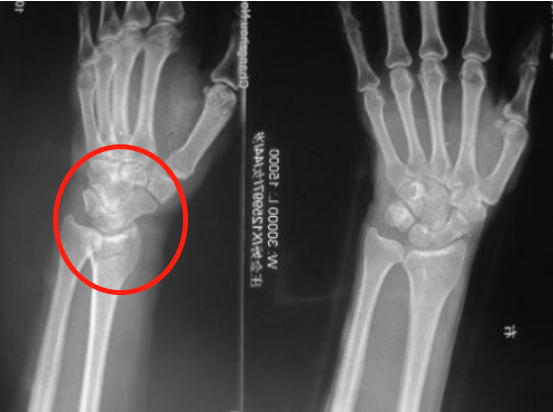

(裂纹型骨折) (移位型骨折) 实际上,“骨裂”究其本质上还是骨折,只不过骨折不移位或移位不明显罢了。换言之,骨裂是骨折的一种类型,而非与骨折相提并论,其治疗原则和其他类型骨折并无差异,都是复位、固定和功能锻炼。 其二,骨裂就是骨折,不固定或固定时间不够依然会出现移位或者骨折延迟愈合、不愈合,千万不能区别对待。说到这里,就不得不提及骨折的治疗原则——“复位、固定、功能锻炼”,虽然只有短短的7个字,却饱含了很多重要的信息。复位是骨折后首要解决的问题,这个复位根据骨折部位不同有的需要功能复位,有的需要解剖复位。总之,骨科医生治疗骨折的第一步就是复位,骨裂的患者这一步自然不用多做。 接下来要解决的问题就是固定,为什么要固定?“固定”解决的问题是复位后骨折断端的维持,所谓骨裂的患者往往骨折断端都没有明显移位,但是这并不代表骨折不会出现继发性移位,因为没有有效固定或者未按医嘱要求固定,导致不得不采取手术治疗的案例临床上也比比皆是,有的患者觉得只是骨裂就掉以轻心、麻痹大意,不遵医嘱佩戴石膏或支具,殊不知这些原则都是用血泪的教训总结出来的,目的就是同样的错误不可再犯,不要去承受这本可避免的痛。 (骨折后石膏固定) 有时候规避风险只需要一个合适的石膏,固定不牢,势必移位,移位之后再手术往往导致错过最佳的锻炼的时间,一来二去就是出现关节僵硬、骨质疏松、肌肉萎缩等这样那样的骨折并发症,而这一切也仅仅是一个石膏就可以避免的。 况且,没有骨折的患者,关节部位的韧带损伤常常也是需要石膏固定的,目的是通过“制动”促进韧带的修复。 总之,石膏固定的目的是在保护或者维持良好的复位,是加分项而非减分项,能用石膏固定解决的骨折说明骨折不算严重,预后还是很好的。 其三,“动静结合”的理念贯穿了骨折治疗的自始至终。石膏固定并非不能活动和锻炼,其固定的只是局部,没有石膏固定的其他部位可以动也鼓励多动,可以避免很多骨折并发症的发生。众所周知,石膏固定限制骨折局部的活动,非石膏固定的区域可自由活动,需注意“上肢不提物、下肢不负重”这一基本要求。 固定骨折局部的目的是为骨折愈合提供一个稳定的内环境,促使其早期纤维连接直至中后期形成内外骨痂实现骨折的愈合。在普通大众看来,带上石膏非常不方便不能洗澡;非常不好看被人嘲笑;非常不舒服不太透气。可是这些理由在我们看来是站不住脚的。 (移位后畸形手术治疗) 骨折本身就是一件麻烦的事情,如果仅仅是怕麻烦而不去石膏固定的话,那很可能会因为图省事而继发的骨折断端移位、延迟愈合、不愈合等并发症,届时增加的就是金钱和时间,而得到的结果是关节的僵硬和肌肉萎缩,细想起来极不划算,这不是人们常说的那句古话:捡个芝麻丢个西瓜,得不偿失啊! 骨折患者的幸福都是一样的而不幸却是各不相同的。在相对简单骨折的治疗中遵循原则、遵从医嘱相信科学、有效固定依然是行之有效的方法。